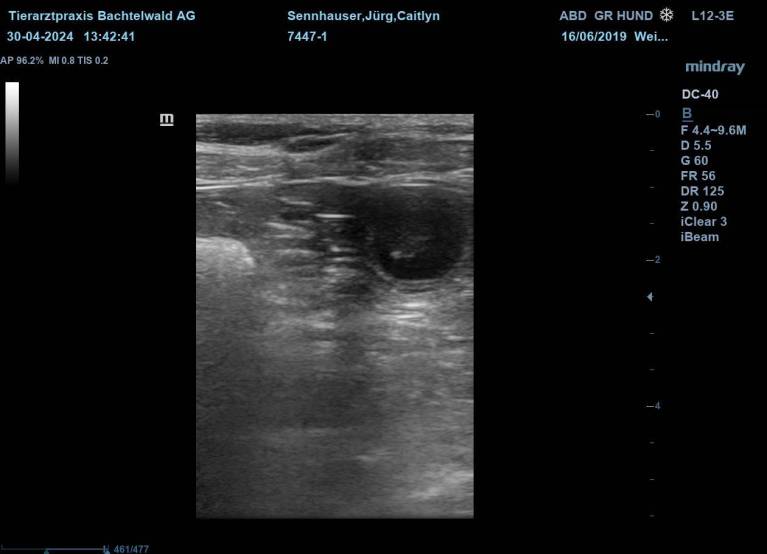

Caitlyn wurde Anfang April mit dem Xanadu "Zane" verpaart.

Nun heisst es "gespannt warten" bis wir in 3 Wochen den Ultraschall machen werden.